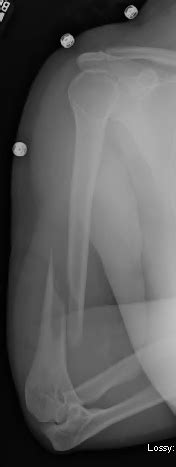

Humerus Spiral Fracture X Ray - Surgical neck of humerus fracture | Image | Radiopaedia.org - Online catalogue product fracture humerus spiral fracture.. Intramedullary nailing of bilateral pathologic humerus fractures. Most humerus fractures are nondisplaced and will heal within a few weeks if arm is immobilized. Mechanism of injury the mechanism of injury is blunt trauma or indirect trauma (including overuse injury in throwers such evaluation: A line spiraling around the entire bone and a longitudinal line linking the proximal and distal portions of the spiral. Communitive midshaft humeral fracture with callus formation.

Distal spiral fracture of the humerus. Online catalogue product fracture humerus spiral fracture. A fracture line may extend into the humerus head with separation of the tubercles. Radiograph of the left humerus shows an humeral fracture spiral midshaft. Oblique mildly displaced fracture shaft of the humerus with superior undisplaced spiral extension to the proximal metadiaphysis.

594 x 800 jpeg 85kb. 231 x 300 jpeg 10kb. The injury was sustained during a fall. A spiral fracture of humerus is supposed to have a good surface area of contact for healing, is likely to be a low energy injury and is relatively more stable than a transverse fracture. Normally two views will be. You may develop a spiral fracture pattern in the humerus due to some twisting injuries. Radiograph of the left humerus shows an humeral fracture spiral midshaft. Mechanism of injury the mechanism of injury is blunt trauma or indirect trauma (including overuse injury in throwers such evaluation: Translated from the original german by ethan taub, m.d. Oblique fracture of the right tibia and comminuted fracture fo fibular head (post external fixation) 13. Torsion fracture) is a bone fracture occurring when torque (a rotating force) is applied along the axis of a bone. Distal fractures are considered with the elbow. From wikipedia, the free encyclopedia.

Types of Fractures with X-ray Examples - Ask The Rad Tech from i2.wp.com Learn vocabulary, terms and more with flashcards, games and other study tools. Most humerus fractures are nondisplaced and will heal within a few weeks if arm is immobilized. A spiral fracture of the humerus shaft. A spiral fracture of humerus is supposed to have a good surface area of contact for healing, is likely to be a low energy injury and is relatively more stable than a transverse fracture. Case contributed by dr mohammad osama hussein yonso ◉. The patient also has philos from old proximal humerus fracture. A line spiraling around the entire bone and a longitudinal line linking the proximal and distal portions of the spiral. The injury can also involve the long bones of the arms, including the humerus, ulna, and radius.